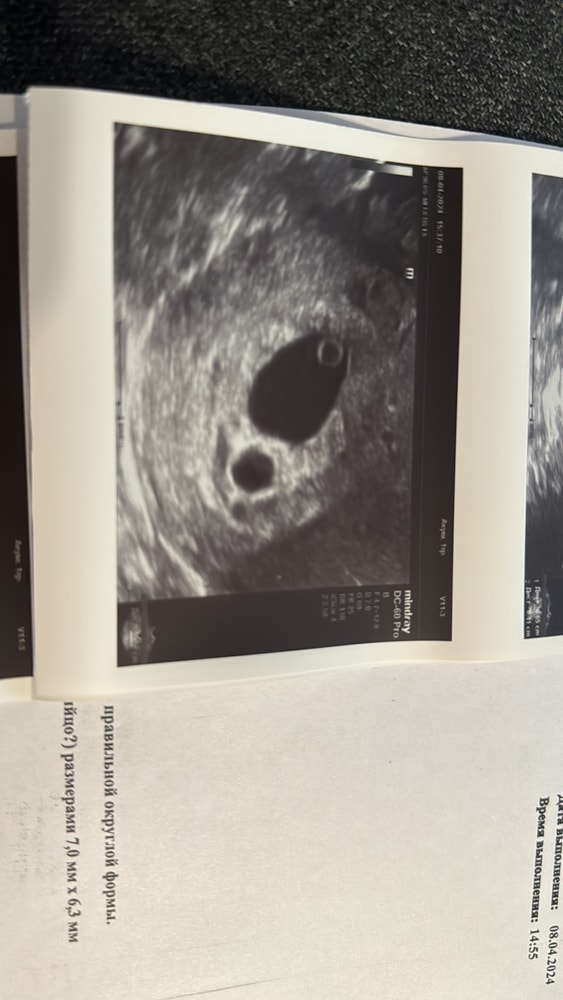

Всем здравствуйте, узнала на 5 неделе что у меня двойня. На 9 неделе сделали УЗИ оказалось что одно плотное яйцо пусто поставили анэмбрионию. Теперь гинеколог отправляет на аборт, хоть я первым ребёнком все хорошо, сердце бьётся, размер соответствует. Направление гинеколог на аборт не даёт, так как показаний нет. Но настоятельно советует избавится от ребёнка. Говорит что скорее всего родится с тяжёлыми патологиями, будет даун или дцп, или не проживёт и 3х месяцев умрёт от каких либо не доразвитостей. Я не знаю что делать. Я боюсь его убивать. Ведь есть шанс что он родится здоровым. Т.е. я должна сейчас убить здорового ребёнка. Плачу 3 день не могу взять себя в руки